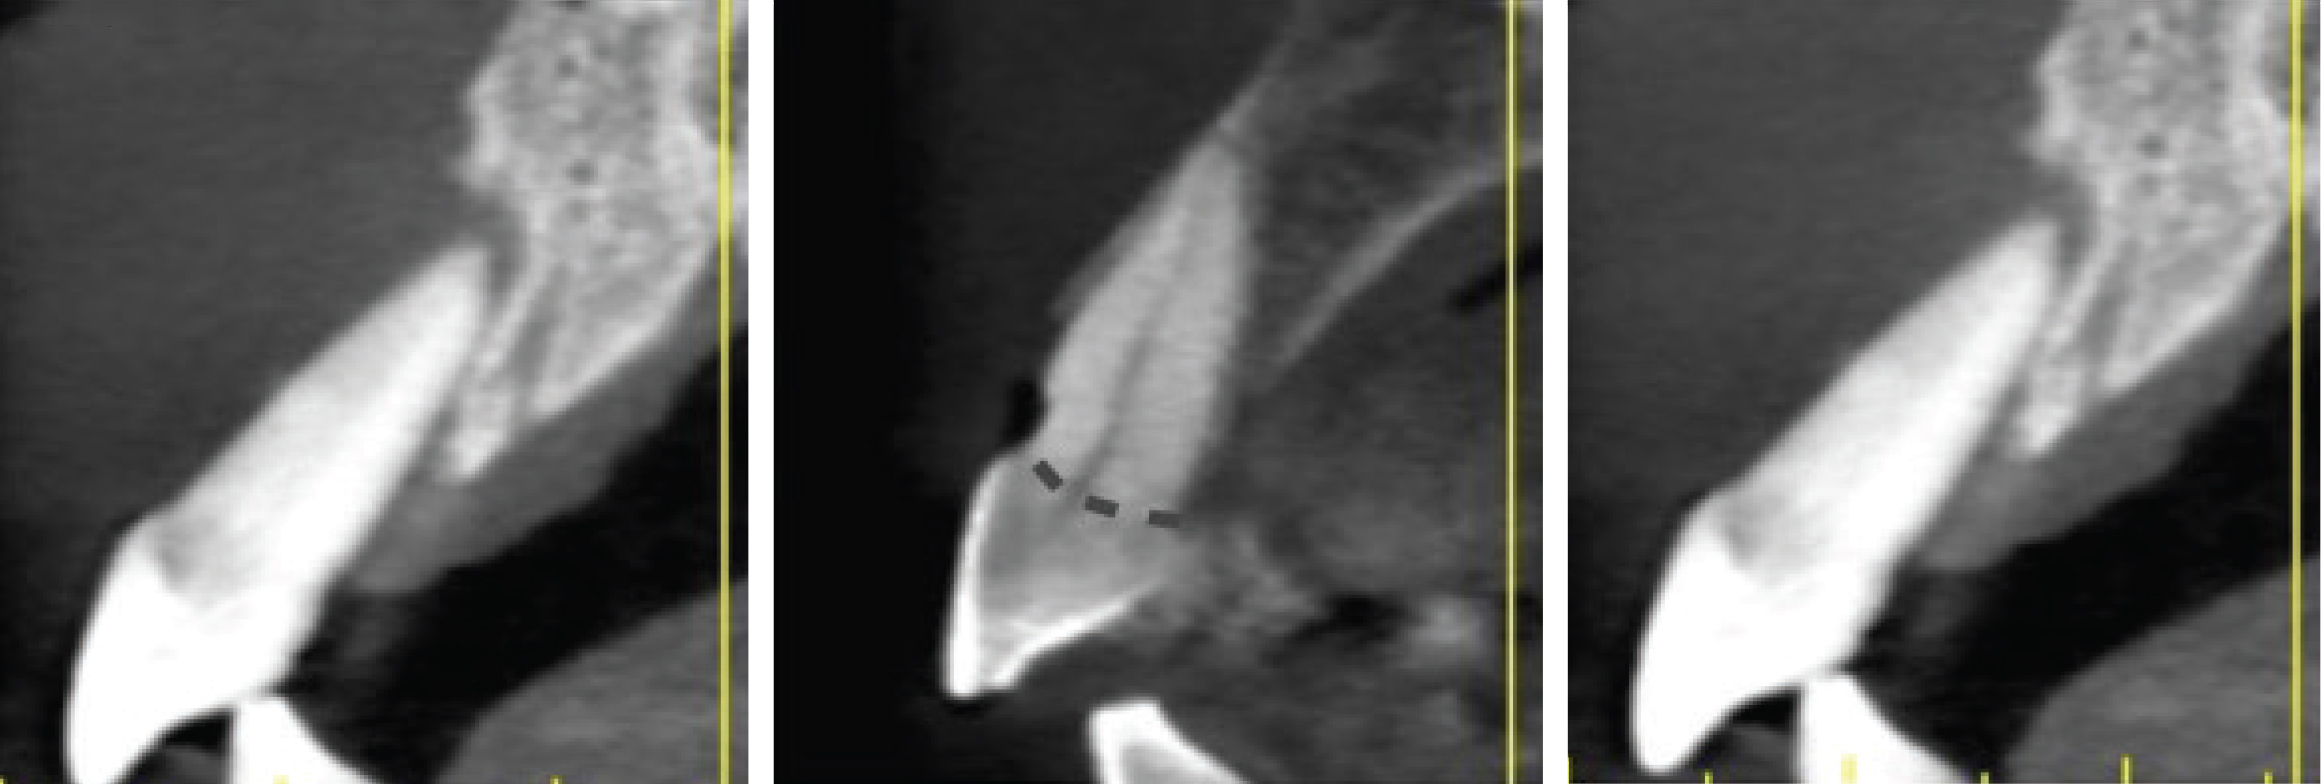

Figure 3

(Left) Grade I socket with an intact buccal plate demonstrating less than 25% bone loss; (Center) Grade II socket showing  ssure, dehiscence, and approximately 50% buccal plate loss; (Right) Grade III socket with more than 50% buccal plate loss.

Figure 4

Sagittal cross-sections of CBCT images depicting Grade I (Left), Grade II (Center), and Grade III (Right) sockets. Note the level of the buc- cal plate relative to the cementoenamel junction that is elucidated by this cross-cut.